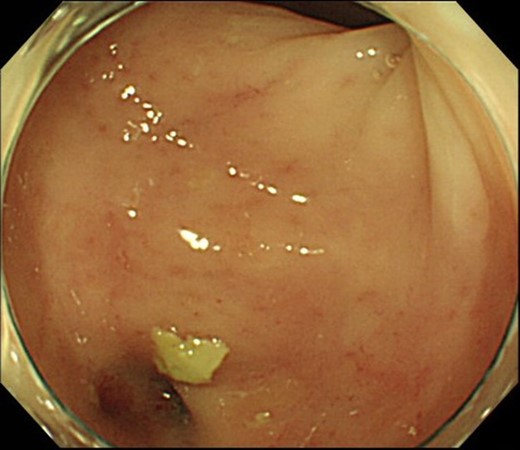

Case 1 was a 71-year-old man with a BMI of 29.7 kg/m2. Laparoscopic low anterior resection (LAR) and ileostomy was performed for rectal cancer in 2017 years. Postoperative fever and lower abdominal pain were noted, and colonoscopy was performed, and anastomotic leakage was noted with a correction of about 1/2 around the 6 o’clock direction of the anastomotic region, and fistula and formation of a large abscess cavity. After identification (Fig. 1), a tube was inserted for drainage and conservative treatment was performed. The patient was discharged on POD 46. Four months after the operation, marked improvement in the abscess cavity was noted but still remained (Fig. 2a and b). Anastomotic leakage was almost improved by colonoscopy at 17 months after surgery, but at the preference of the patient we performed colostomy 22 months after surgery (Fig. 3). It took a long time to improve intestinal movement of the colon because the large intestinal tract had not been used for a long time, and conservative treatment was performed using a nasogastric tube for paralytic ileus. Diet was initiated 7 days after surgery, and the patient was discharged from the hospital 14 days after surgery. The Wexner score [2] was 19 points one month after closure, 17 points 3 months after the operation and 16 points after 6 months after the operation, and severe anal dysfunction was observed, but gradually improved.

Colonoscopy revealed a true lumen (circle), an anastomotic site (triangle) and a cavity due to suture failure (arrow).